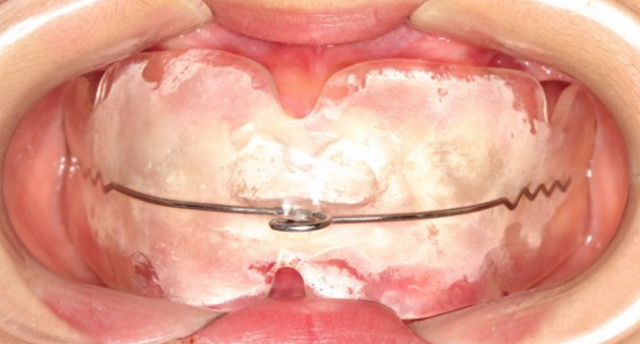

黃丞一副主任醫(yī)師仔細(xì)檢查后發(fā)現(xiàn),孩子的門牙突出,上頜牙弓特別狹小,整排牙齒都非常不整齊。

雖然當(dāng)時(shí)接診時(shí),小林的腺樣體腫大已經(jīng)存在了一段時(shí)間,不過幸好發(fā)現(xiàn)及時(shí)。根據(jù)黃醫(yī)生的建議,小林及時(shí)到耳鼻喉科做了腺樣體摘除術(shù),并且認(rèn)真地進(jìn)行肌功能訓(xùn)練,對(duì)已經(jīng)凸出的牙齒進(jìn)行矯正。

首先,輕度腺樣體腫大一般用抗炎藥物控制就可以了。中度和重度的腺樣體腫大可以先用抗炎藥物控制一個(gè)月;如果效果不好,就需要手術(shù)切除腫大的腺樣體。小林的腺樣體腫大已經(jīng)存在了一段時(shí)間,不過幸好發(fā)現(xiàn)及時(shí),小林及時(shí)在邵逸夫醫(yī)院耳鼻咽喉頭頸外科做了腺樣體摘除術(shù)。

第三,如果已經(jīng)發(fā)生了口腔錯(cuò)合畸形,就需要根據(jù)不同的錯(cuò)合畸形類型進(jìn)行功能性矯正和后期的固定矯正了。